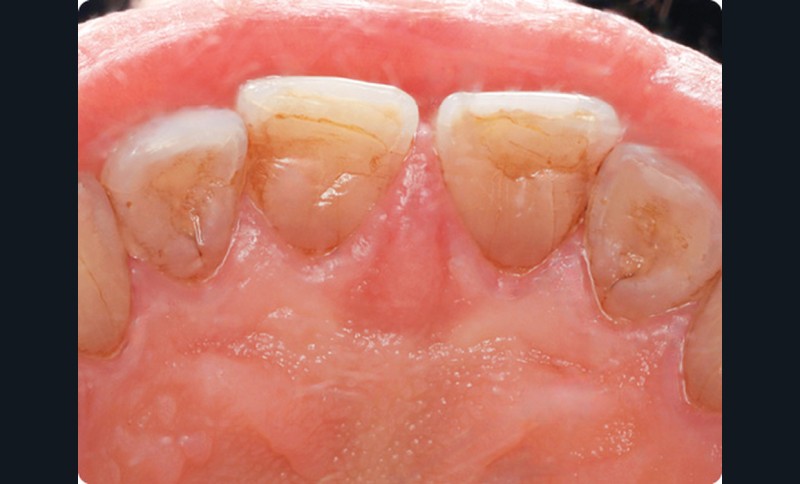

• Dans la région palatine médiane antérieure, on observait une tuméfaction limitée à la papille palatine. Cette dernière, douloureuse à la palpation, était recouverte par une muqueuse érythémateuse. Les dents 11 et 21 étaient vivantes et elles ne présentaient pas d’atteinte parodontale active.